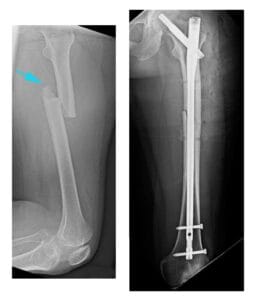

X-ray shows a transverse fracture of the femur. The break is a straight horizontal line across the shaft.

(Left) This X-ray, taken from the side, shows a transverse fracture of the femur. (Right) In this front view X-ray, the fracture has been treated with intramedullary nailing.

Intramedullary Nailing

Intramedullary nailing is currently the preferred method for treating femoral shaft fractures. This procedure involves inserting a specially designed metal rod, or nail, into the femur’s canal. The nail spans the fracture site, stabilizing the bone and promoting proper alignment during healing.

Intramedullary Nail Placement

The intramedullary nail can be inserted at either the hip or knee end of the femur. Screws positioned above and below the fracture maintain proper alignment as the bone heals. Intramedullary nails are typically made of titanium and come in various sizes to fit different femur dimensions.

Intramedullary nailing provides strong, stable, full-length fixation.